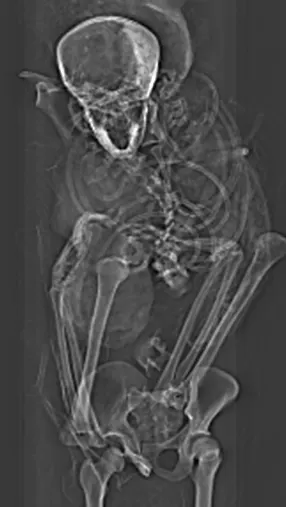

A CT scan study of the mummy of Pharaoh Seqenenre-Taa-II, an Egyptian ruler whose death eventually helped reunite the kingdom, revealed new details about how the king died. A recent paper suggests that the pharaoh died close to the battlefield and was ceremoniously executed by several people using Hyksos weapons. Additionally, the computer-processed x-rays revealed his embalmers had skillfully concealed some of the wounds, implying professional mummification of the body, despite its poor preservation.

The authors of the new paper offer a novel interpretation of the events before and after the king’s death based on the computer-processed x-ray images: Seqenenre had indeed been captured on the battlefield, but his hands had been tied behind his back, preventing him from defending against the attack.

For example, the CT scans, combined with other evidence, suggest the execution had been carried out by multiple attackers, which the scientists confirmed by studying five different Hyksos weapons that matched the king’s wounds.

In addition, the CT study revealed important details about the mummification of Seqenenre’s body. For instance, the embalmers used a sophisticated method to hide the king’s head wounds under a layer of embalming material that functioned similarly to the fillers used in modern plastic surgery. This would imply that mummification took place in a real mummification laboratory rather than in a poorly equipped place, as previously interpreted.